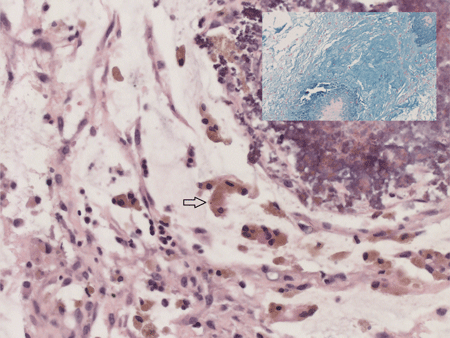

At 6 weeks of age she was referred to us with bilateral incarcerated inguinal hernias. She had no evidence of bowel obstruction and clinically there were firm masses on both groins suggesting ovary as the most likely content. Bilateral inguinal herniotomy was carried out promptly. However, Intra-operatively on either side the inguinal hernial sacs contained omentum attached to an irregular, grey coloured mass with nodules distally. This mass was excised, healthy omentum returned and a standard herniotomy carried out on both sides. Post-operatively she recovered well and was discharged the following day. Histopathological examination confirmed the excised mass to be made up of omentum with areas of dystrophic calcification reminiscent of the saponification with mucin and meconium-laden macrophages; consistent with antenatal perforation of intestine (Fig. 1). At 3 months of follow-up, she remains well and opening her bowels regularly.

Figure 1: Histological images of omental mass excised during inguinal herniotomy in our patient displaying omentum with meconium-laden macrophages (arrow), Haemotoxylin and Eosin stain, magnification X40; [Inset displaying mucin, stained with Alcian blue, magnification X10]